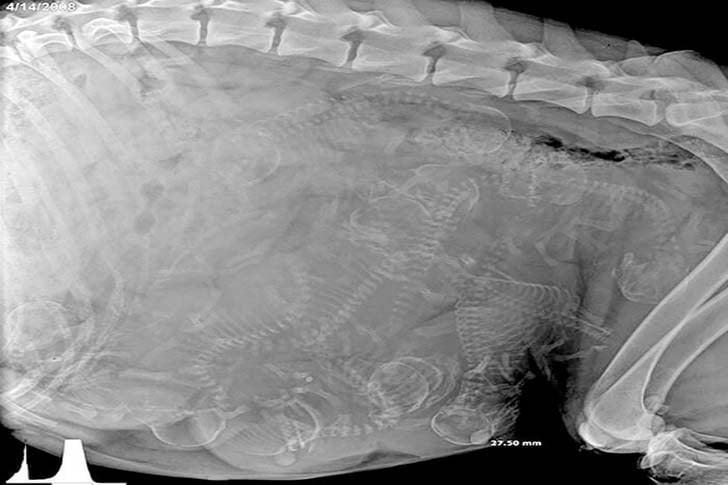

Si cette photo n’avait pas de légende, vous pourriez imaginer tout un tas de scénarios pour expliquer cet amas d’innombrables petits os dans un seul grand corps. Mais une fois que vous connaissez le contexte, c’est en fait assez incroyable. C’est choquant de voir autant d’os entassés dans un espace aussi restreint et de réaliser que c’est “naturel”. Figurez-vous que ce sont tous des chiots qui sont sur le point de naître !

Bien que les échographies pendant la grossesse humaine soient une vision familière, les radiographies d’une chienne gestante ne cessent de nous étonner.